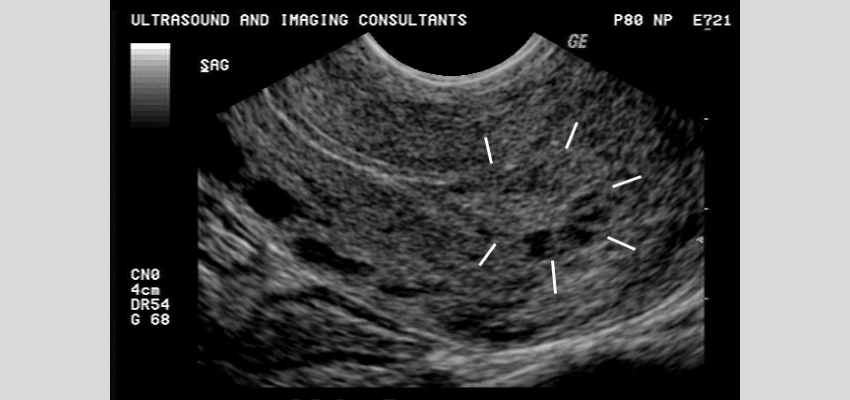

Çoğu döllenmeden itibaren birkaç hafta içinde fark edilir. Üzüm gebeliği ultrason muayenesi ile teşhis edilir. Ama öncesinde belirtileri olan kadınlarda HCG hormonunun seviyesi ölçülür. Bu seviye fazla çıkarsa genellikle ultrasona geçilir.

Mol gebelikte ultrason görüntüsü "kar yağdı manzarası" görünümündedir.